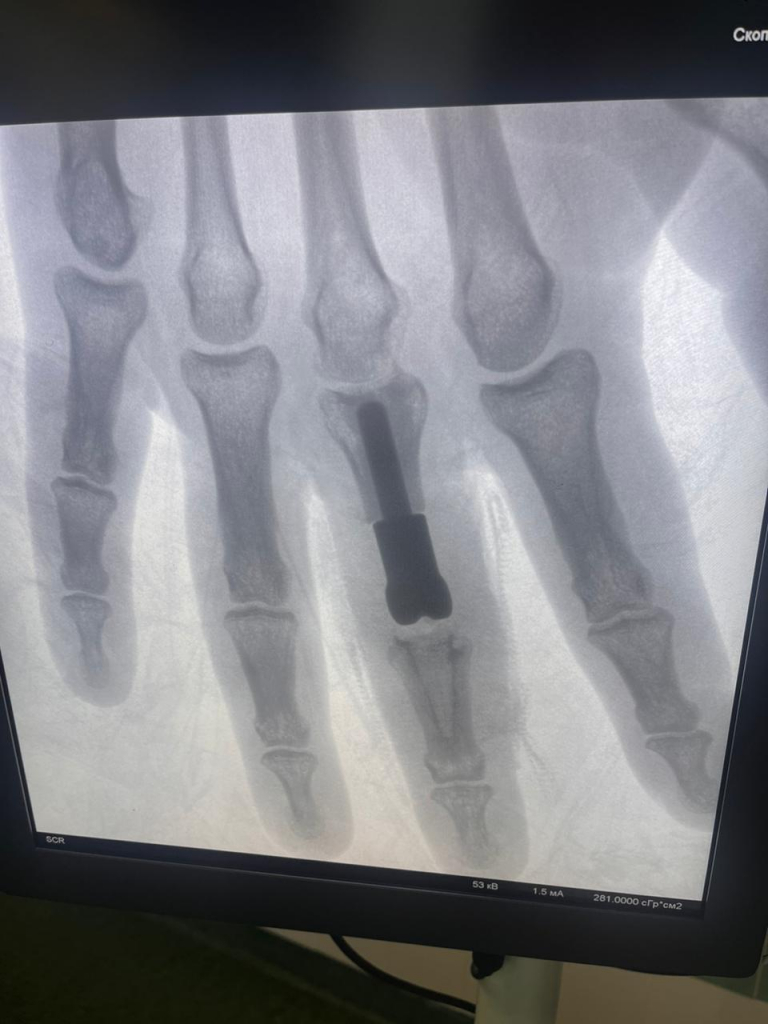

К хирургам-травматологам попал мужчина с открытым оскольчатым внутрисуставным переломом 3 пальца правой кисти. Это тяжелое повреждение, затрагивающее не только кости, но и межфаланговый сустав. Также были травмированы сухожилия, участвующие в разгибании пальца, и покровные ткани.

Такую травму невозможно вылечить стандартными способами (гипсовая повязка, остеосинтез). В случае открытого, мелкооскольчатого перелома, когда восстановить суставные поверхности не представляется возможным, необходима замена поврежденного сустава на протез. Но площадь поражения костей пальцев у пациента была значительной, установка стандартного эндопротеза привела бы к укорочению пальца и неудовлетворительному окончательному результату. А это, напомним, правая, доминирующая рука.

Врачи пришли к решению о необходимости изготовления индивидуального эндопротеза, который смог бы заменить не только сам сустав, но и восполнить дефект основной фаланги пальца.

«Протез, высокотехнологичный имплант, был изготовлен с применением аддитивных технологий. Если мы привыкли, что традиционно детали изготавливаются путем «вычитания» лишнего материала из заготовки, то в основе аддиктивных технологий, напротив, лежит принцип «добавления». Протез был «напечатан» из титанового порошка на 3d принтере. Полученная конструкция учитывала все малейшие нюансы и особенности, которыми должен обладать имплант, предназначенный для конкретного пациента. В России в настоящее время есть уже несколько биометрических лабораторий, которые занимаются подобной инновационной деятельностью.

За точность размеров компонентов и их форму отвечал биоинженер. Задача хирургов заключалась в установке созданного эндопротеза и проведении пластики поврежденного сухожилия. Операция прошла успешно», – рассказал о проделанной работе хирург-травматолог Алексей Сизиков.